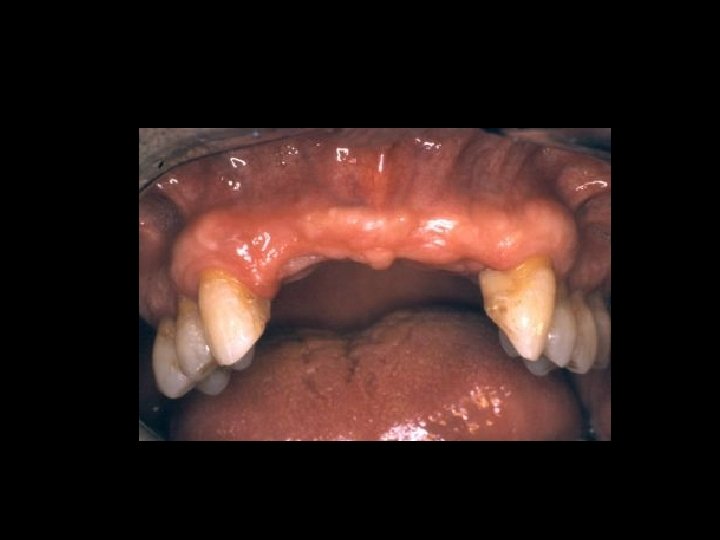

Responsabilità Garanzia di mezzi Ø Garanzia di risultato Ø Scelta del tipo di trattamento Ø Ø Condizioni denti Ø Condizioni delle mucose Ø Condizioni delle ATM Ø Preparazione dei denti pilastro Ø Prospettive di risultato estetico Ø Prospettive di risultato nel tempo Ø Caratteri del manufatto